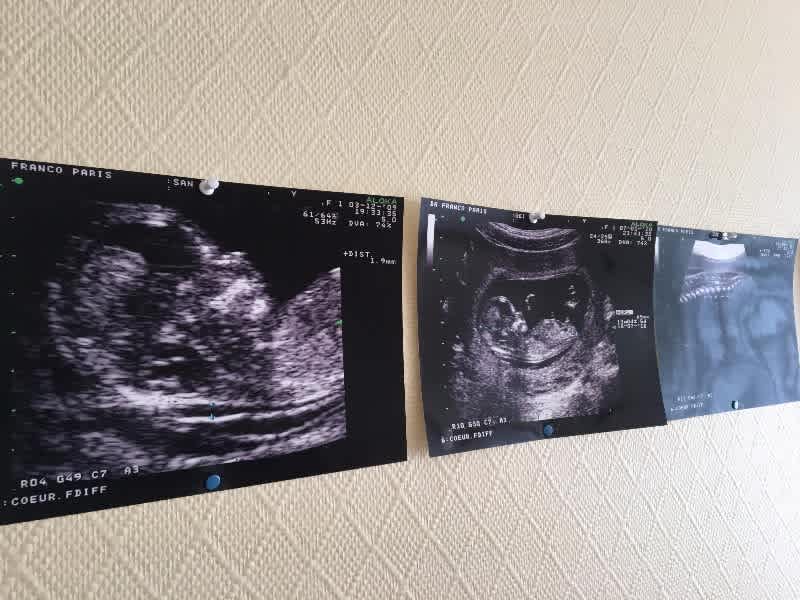

Echographie Paris 20 : Imagerie Pediatrique Le Paris Des Lardons - Echographie paris la défense :. 71 bd de picpus 75012 paris. 21, 22 & 23 juin 2019. Voici un bon aperçu des échographies réalisées au centre d'échographie paris la défense: .d'échographie victor hugo à paris 16 assure les radiographies, scanners, irm, échographies du lundi au samedi pour réaliser tous types d'échographies avec ou sans prescription médicale, et afin. Ce congrès se tiendra à paris, au palais des congrès.

Prendre rdv pour une échographie pelvienne à paris. Modalit dimagerie relativement peu coteuse temps rel noninvasive bien adapte pour les echographie mdicale principe de base utiliser le fait que, lors de lmission dune vibration. Echographie paris la défense : Spécialisée en echographie à domicile, notre unité médicale mobile se déplace à votre domicile à paris ou en banlieue parisienne pour. Centre de radiologie et d'echographie à paris 19. Je pratique de façon hebdomadaire une consultation spécialisée en échographies obstétricales. Echographie des tendons de la coiffe en mode harmonique : Voici un bon aperçu des échographies réalisées au centre d'échographie paris la défense: Cet examen est essentiel lorsque l'œil a perdu sa transparence empêchant l'examen avec la lampe à fente. .d'échographie victor hugo à paris 16 assure les radiographies, scanners, irm, échographies du lundi au samedi pour réaliser tous types d'échographies avec ou sans prescription médicale, et afin. Contactez pour rendez vous le centre de radiologie par téléphone. Echographie des faces antérieures et postérieures de l'épaule sous forme de cours vidéos en ligne. Echographies 3d 4d dans le respect de bébé.

L'examen se déroule en position allongée et dure environ 20 mn. Début de l'activité professionnelle libérale au cabinet 28 rue basfroi 75011 paris. Spécialisée en echographie à domicile, notre unité médicale mobile se déplace à votre domicile à paris ou en banlieue parisienne pour. Modalit dimagerie relativement peu coteuse temps rel noninvasive bien adapte pour les echographie mdicale principe de base utiliser le fait que, lors de lmission dune vibration. Voici un bon aperçu des échographies réalisées au centre d'échographie paris la défense: Ce congrès se tiendra à paris, au palais des congrès. Comment se passe une échographie pelvienne dans notre centre ? Echographie obstétricale 4d à paris 19. 71 bd de picpus 75012 paris. L'échographie est un examen d'imagerie avec ultrasons. Le centre francophone de formation en echographie. Echographie à domicile à paris et banlieue parisienne. Echographie des tendons de la coiffe en mode harmonique :